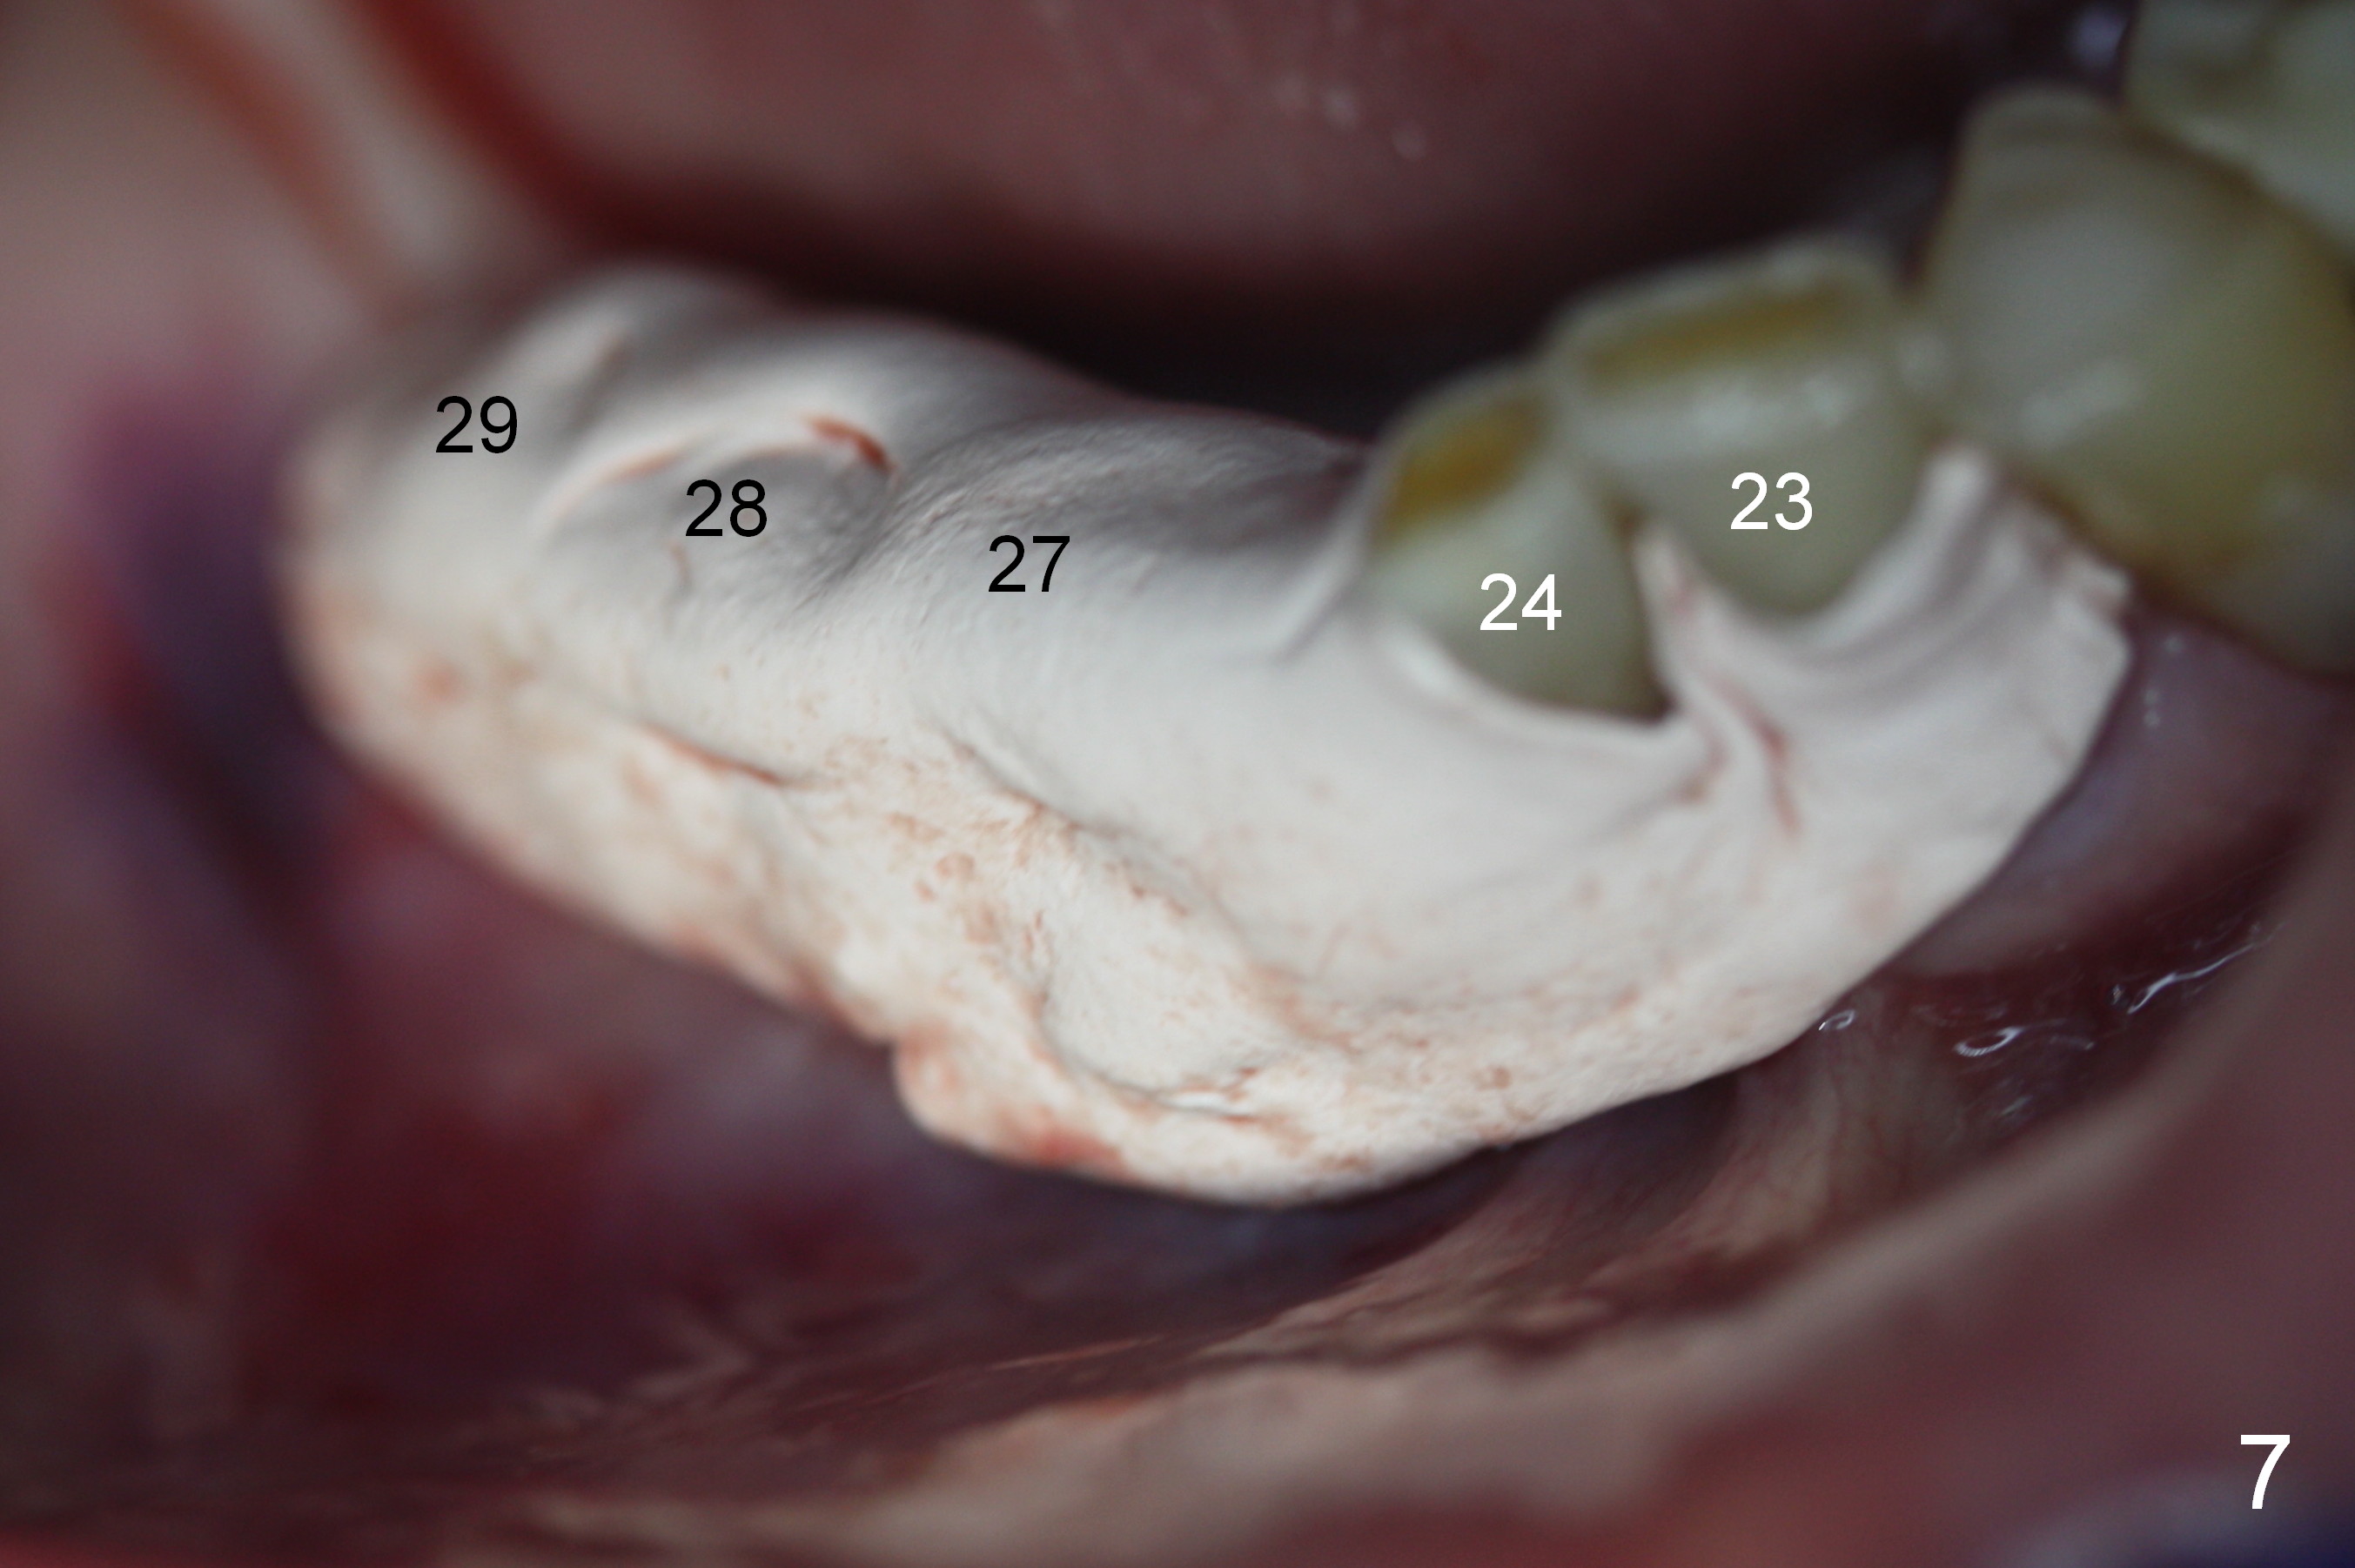

A 86-year-old man returns to office for the lower right quadrant reconstruction with implants. In addition to the immediate ones at the sites of #27 and 28 (Fig.1), how many and where else? The patient reveals that he does not plan to get an implant at the site of #3 (Fig.2). Therefore there is no need for an implant at #30. Preop CT shows that bone width is compromised at #26. So the 3rd site will be #29 (Fig.3,4). All of the 3 implants (4.5x14 mm, 4.5x12, and 4.1x12 mm) achieve primary stability (»55 Ncm). An immediate provisional could be provided, but it seems difficult to close the buccal (Fig.5 B) gaps of #27 and 28 after bone graft with the provisional. In contrast, the gingiva adapts to the implant at #29 well (Fig.6 B). Perio dressing is applied to the abutments (Fig. 7: #27-29), the edentulous space at #26 and the neighboring teeth (#23,24). It would be ideal to apply a non-resorbable membrane to the buccal opening at #27,28 (Fig.8 white line) prior to perio dressing placement. In case of dislodgement of the latter, the membrane is able to keep bone graft in place.

Eight days postop, the most anterior portion of the perio dressing is dislodged; the rest is stable (Fig.9). Since the patient has difficulty in coming to office, the perio dressing is removed. While the buccal gap of #27 has closed apparently (Fig.10 ^), that of #28 not (*). To prevent irritation from the abutments, a splinted provisional is fabricated (Fig.11 P). Perio dressing should have been re-applied buccal to the gap at the site of #28 or preferably the original perio dressing should have not been removed prematurely.